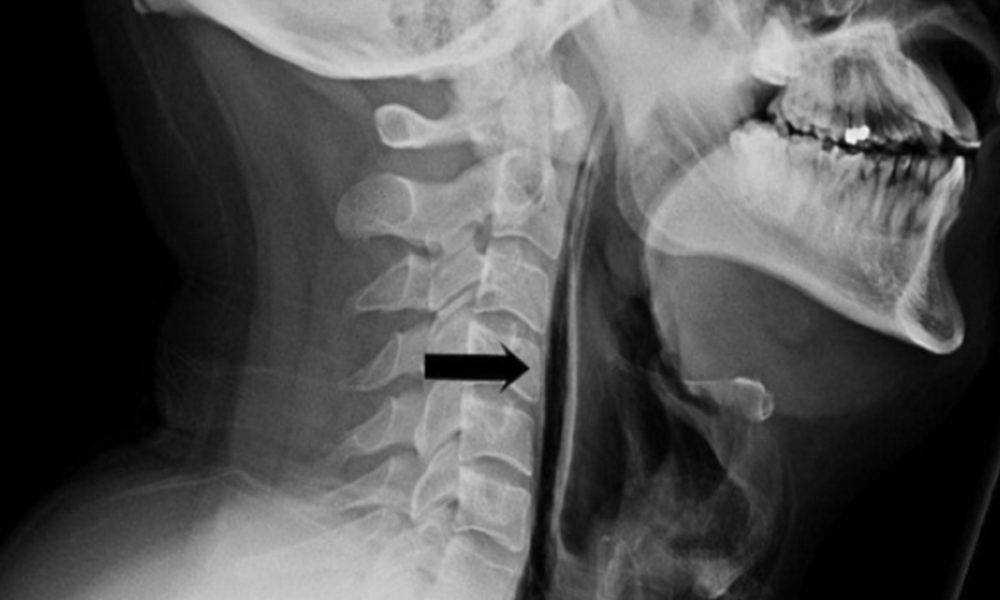

Басылмалардын маалыматына караганда, 34 жаштагы киши катуу чүчкүргөндөн кийин ооруканага түшкөн. Ал чүчкүргөнү жатканда манжалары менен мурдун кармап турган. Кийин мойну шишип кеткен. Ал рентгенге түшүп, кекиртеги айрылып кеткенин билген.